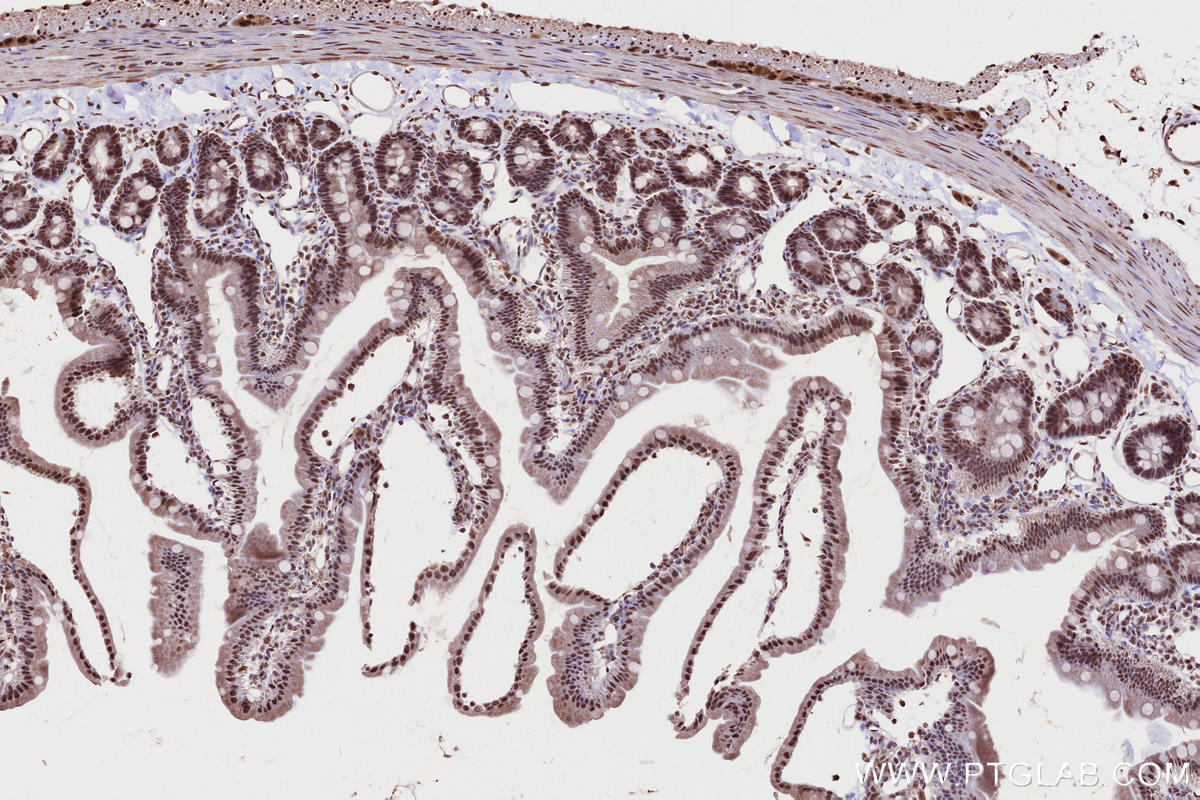

Validation Data Gallery